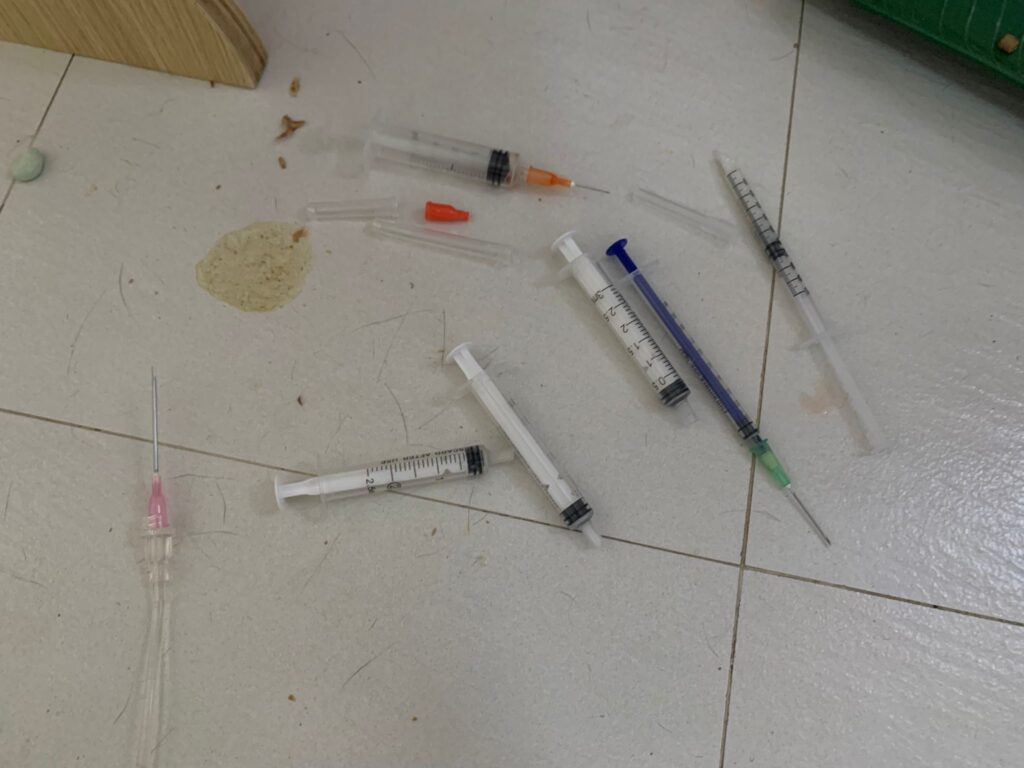

2pm+: checked on him, is right ear got one line, quite deep, bleeding but alr stop. Will give him 5 days ab 0.2ml clav to play safe. Given Subcut n bupre 0.2ml. 3.99kg – gain 80g in a month. Got walk about to eat

10am+: b4 I Subcut n give painkiller still eating ok. Subcut and given b12 b com bupre and put on a f patch (end 1.3.24)

Noon: 3.91kg – lose 210g in 1 week. Subcut him w B12 n b com. N bupre. More vocal but in pain can’t think of reason to go clinic other than status check

12pm+: 4.12kg – gain 50g in 2 months. On regular maintenance Subcut and bupre n b12. and dental care

Morning: given Subcut w b12 b com. N bupre

Morning: Subcut w b12 and Buprenophine

Morning: Subcut w b12 and Buprenophine

Morning: Subcut w b12 and bupre.

Given sc, bupre, fer, b12 and b com, doxy.

Subcut w b12. N bupre. Given Cerenia drops

2pm+: I go back check on their well-being. He welcome me as usual at the door. Sayang him and Subcut, given bupre. Stop urosofalk. Given Cerenia nose drop, he is very ok w it. Given doxy he don’t like n run away.

Morning; 4.04kg – looks thin but gain 50g in 12 days. Given Subcut n b12 n bupre 0.2ml and ursofalk and gaba too.

Morning: given Subcut, b12 and bupre jab. Ursofalk as usual. Eating well. Didn’t fatten

Noon:4.21kg, lose 70g in 3 weeks. Given Subcut, b12 b com jab, ornipural n niramine.

Subcut w B12 b com, Clav, day 03.

2pm+; given Subcut b12 b com, w Clav n usual meds. Given probiotics and Sam e and gaba cream.